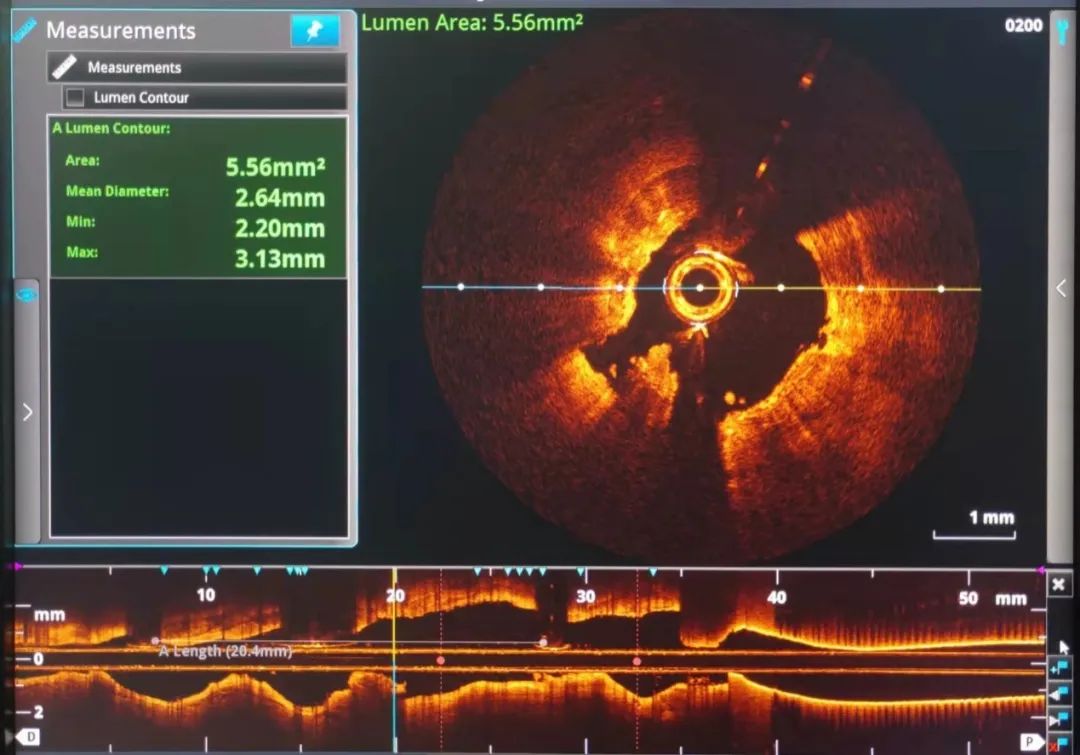

经过充分的术前准备,术前OCT检查提示:前降近中段钙化病变处可见90-360°环形钙化,钙化厚度约0.38mm-0.6mm,长度约10mm,局部可见钙化小结。较厚的环形钙化是导致上次手术使用高压球囊及切割球囊无法顺利打开病变的原因。针对病变特点,在OCT的精确定位下,启用3.5x12mm Shockwave冲击波球囊技术在环形钙化处精准震荡扩张,启动脉冲发生器,持续激发脉冲10S,可见球囊逐渐膨胀充分,随后以6atm扩张震波球囊,可见球囊扩张满意。重新定位冲击波球囊,重复脉冲3个周期共4个周期脉冲优化震波碎裂疗效,复查OCT清楚可见环形钙化斑块碎裂松解,局部未见明显夹层,获得较大管腔,满足支架植入条件。成功于左前降支近段植入3.5mm*13mm药物洗脱支架1枚。

Shockwave球囊治疗前后OCT成像对比:

Shockwave球囊治疗前

Shockwave球囊治疗后